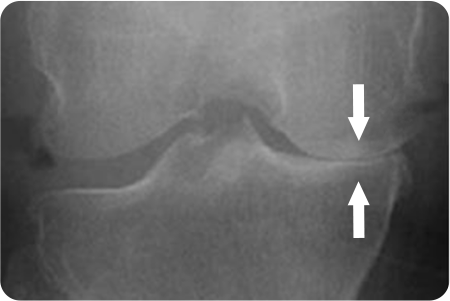

부분치환술

부분치환술 관련 이미지

• 무릎 내측에만 관절염이 있는 경우

• 전방십자인대의 기능이 살아있는 경우

• 다리변형이 10도 이내인 경우

• 다리 구부리고 펴는 것이 일정각도 이상 가능한 경우